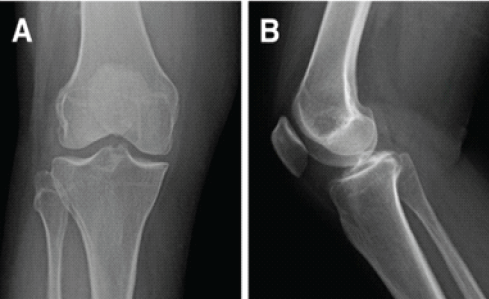

Pre-operative standard knee radiographs were unremarkable, and a scanogram demonstrated normal lower limb alignment (Figs. 1 and 2).

Figure 1: Figure showing normal anteroposterior and lateral view of knee joint.